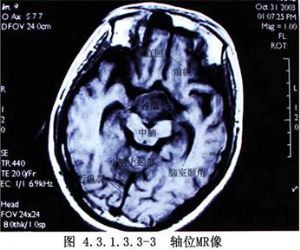

近年來,由於顯微神經外科技術的提高,經翼點入路在顱內腫瘤及動脈瘤手術中的應用日益廣泛。對顱咽管瘤切除術而言,由於這種入路稍加改變就能充分地顯露視交叉前後、視神經-頸內動脈間隙及頸內動脈外側間隙,甚至小腦幕邊緣及頸內動脈分叉部附近的結構,故其適應證較寬。有人(Yasargil,1990)將其用作切除各種顱咽管瘤的主要手術入路(圖4.3.1.3.3-1~4.3.1.3.3-4)。